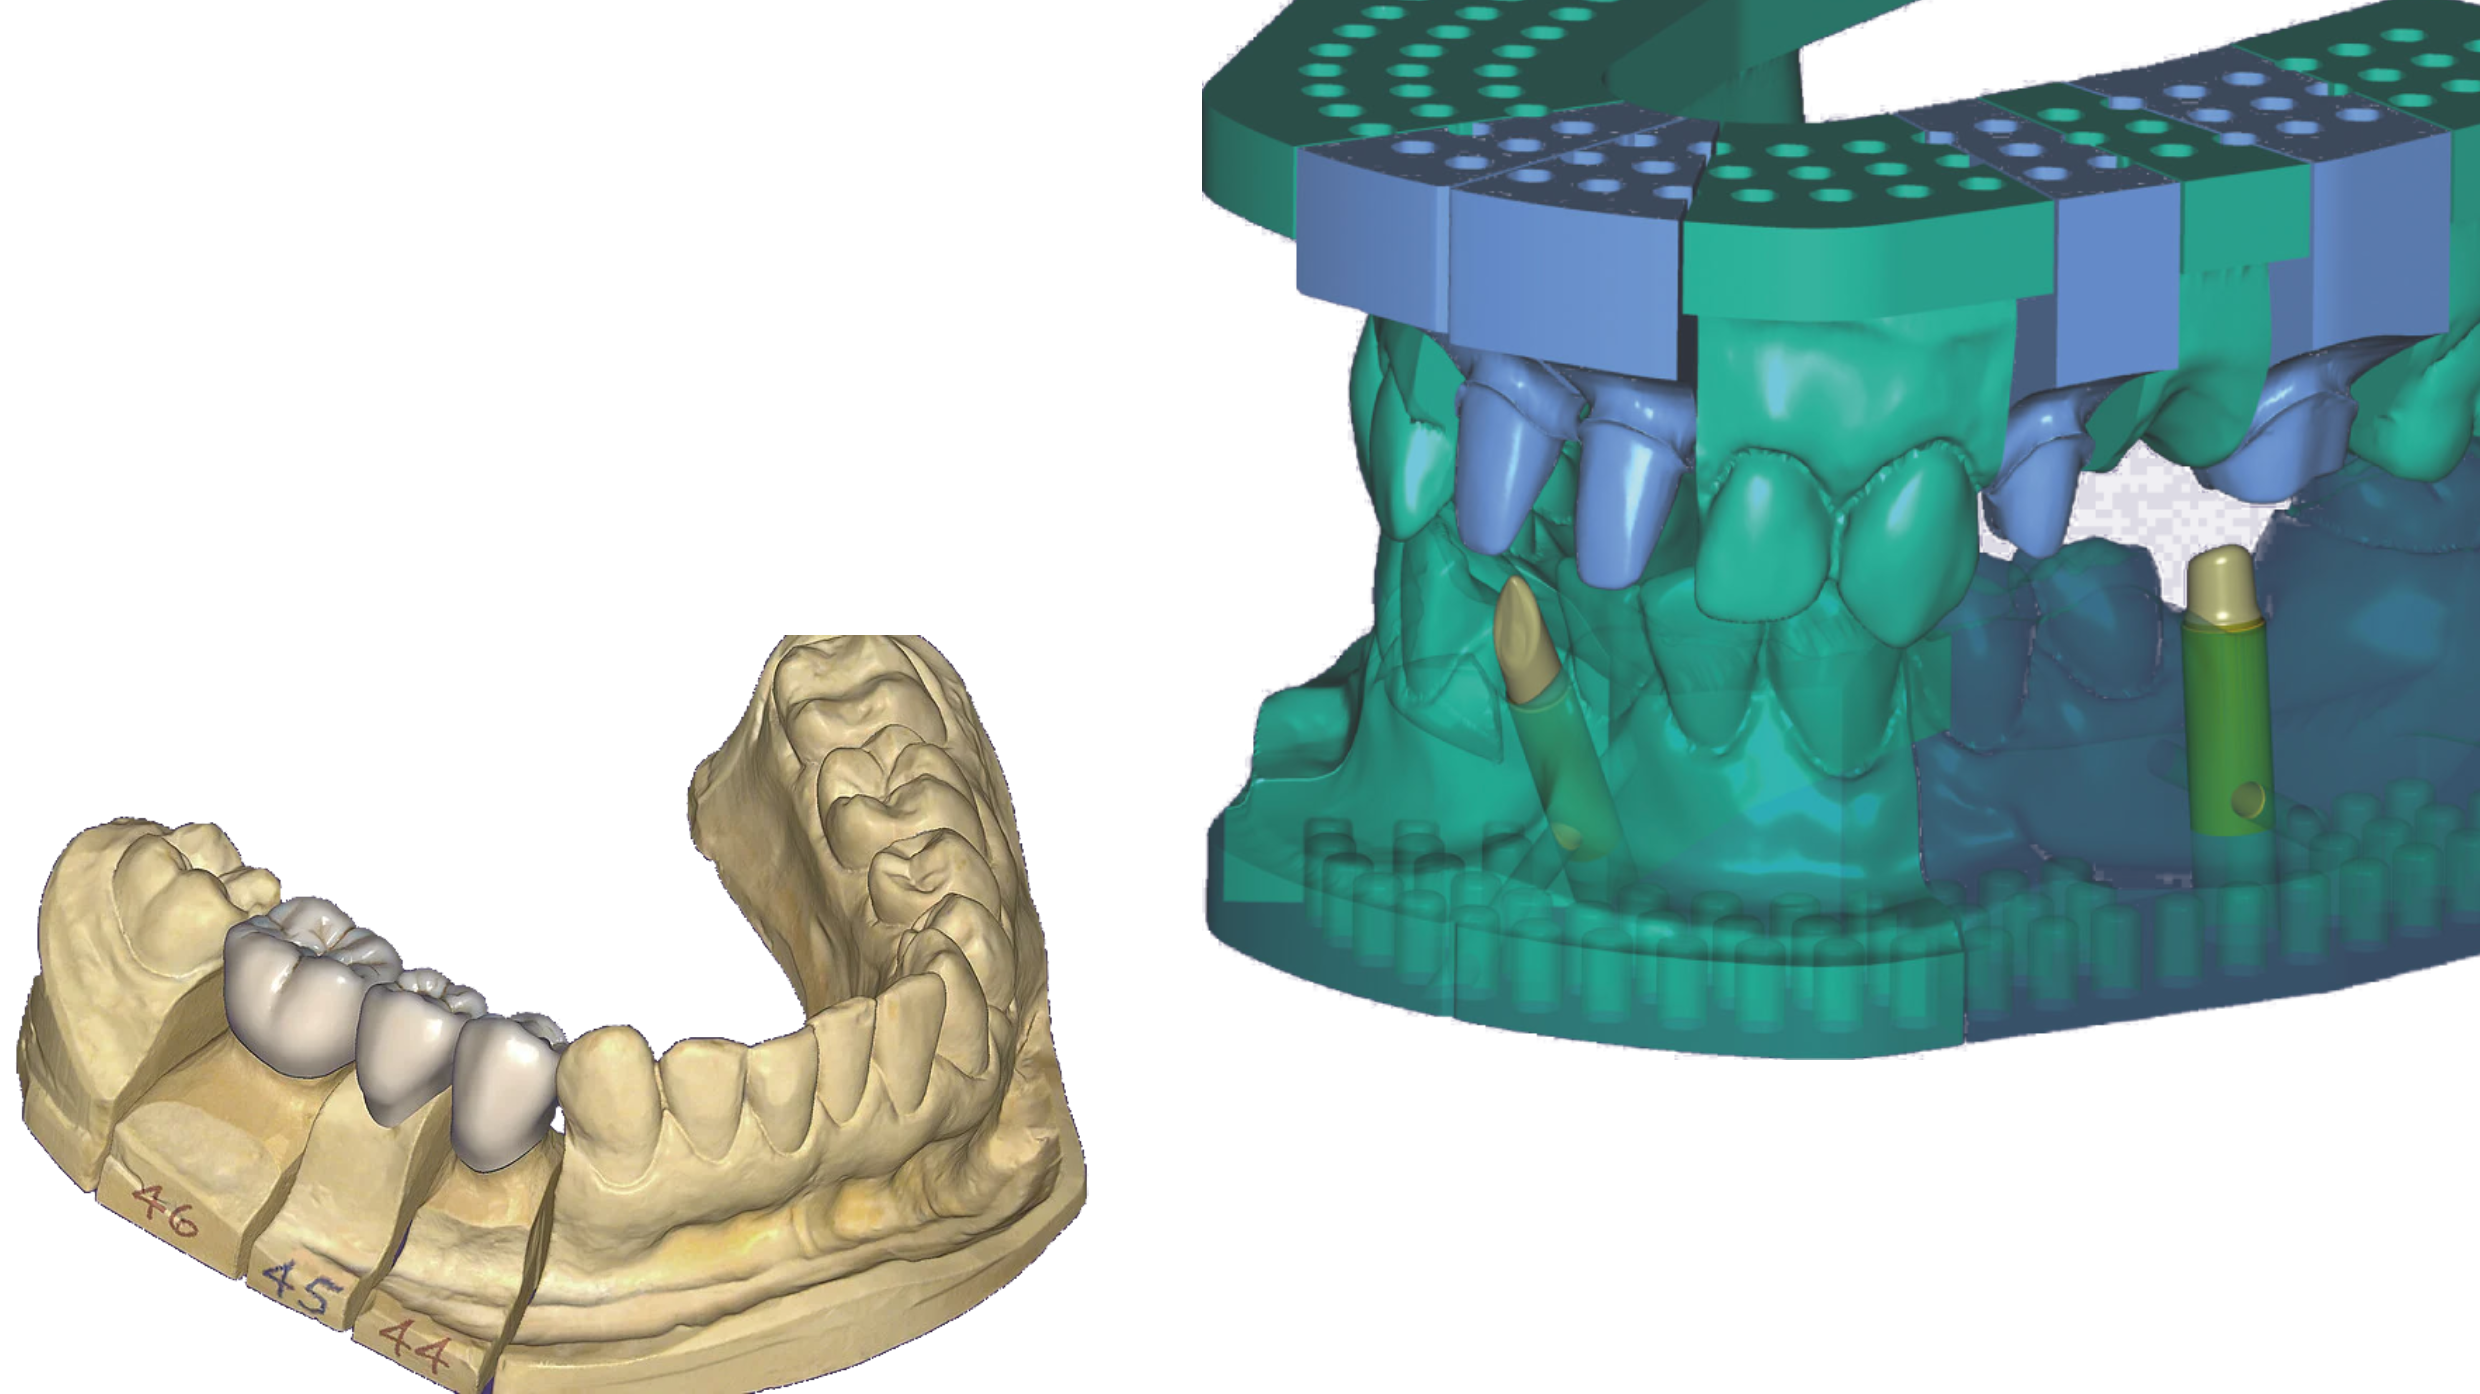

Teo Dent je savremena zubotehnička laboratorija iz Novog Sada, specijalizovana za preciznu i estetsku izradu protetskih radova. Kombinujemo iskustvo, digitalnu tehnologiju i vrhunske materijale kako bismo stvorili prirodne osmehe koji traju.